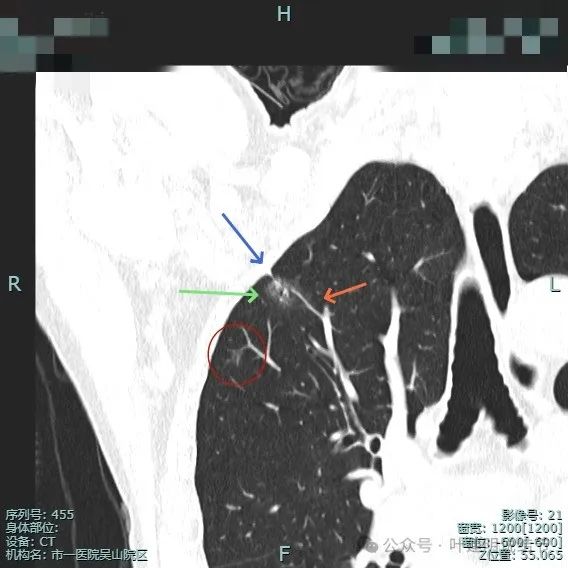

病灶混合密度,毛刺典型,灶内密度紊乱,表面分叶,有较多小空泡征,胸膜略有牵拉。

血管进入病灶,磨玻璃成分较淡,边缘不平毛糙多毛刺、胸膜有牵拉,表面分叶征明显。

实性成分较多,表面不平,磨玻璃部分较淡,血管进入与穿行,胸膜牵拉可见,距其不远有次病灶也是淡磨玻璃密度,轮廓较清,也考虑是肿瘤范畴的,当然风险仍低。